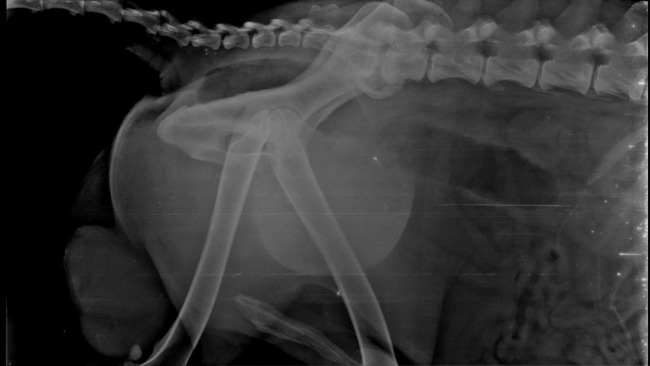

W piatek 29 marca Mikolaj mial robiony tomograf na zdjeciu lezy w poczekalni ,bardzo slabiutki .Ewa nie jest w stanie sama jego dziwgac pomaga jej wspanialy czlowiek pan Krzysztof Tarasek i tu chcialabym mu bardzo podziekowac za pomoc .Koszt to 1800.

Wczoraj 26 marca Mikolaj bardzo zle sie poczul ,Ewa pedzila z nim do kliniki ,skierowano go na tomograf glowy ,guza pluc ,trzeba sprawdzic jak gleboko siega guz ,czy nie ma naciekow na miesnie i kosci .Prawdopodobnie dlatego Mikolaj jest taki slaby .BARDZO PROSZE O WPSARCIE BO KOSZTA ROSNA .

Mamy pierwsze wyniki po tomografie Mikolaj nie ma pzrezutow do mozgu ,ani na plucach ,guz na nodze nie jest naciekowy ,tyle narazie wiemy . Dokladny opis pod koniec tygodnia i wtedy podejmiemy decyzje kiedy operacja .Ogolnie Mikolaj jest slabiutki ..,ale to kwestia czasu powoli dojdzie do siebie .

Opis badania ; zwierze w zlej kondycji ,drzenia glowy ,silne oslabienie ,nie potrafi sam ustac ,oslabienie odruchu zwieracza odbytu ,kal luzny ,koloru pomaranczowo - rozowy ,swiadomosc zachowana .

Jama ustna -silne starcie krony zebow ,dostepne w badaniu wezly chlonne niepowiekszone .Okrywa wlosowa w zlej kondycji ,zmiany skorne - ropne zapalenie skory .Na prawym posladku guz wielkosci pomaranczy ,gruczolak odbytu .Powloki brzuszne miekkie ,niebolesne ,jadra niesymetryczne.

Zmiany na sledzionie - wskazana jest splenektomia ze wzgledu na rozleglosc zmian ,mniej zalecana biopsja .Zapalenie prostaty z przerostem ,kamica pecherza moczowego .

Mikolaj jest bardzo chory ,ma guza na nodze ,guzy na jadrach ,powiekszona sledzione , zwyrodnienie kregoslupa , tyle tych schorzen ze serce peka .